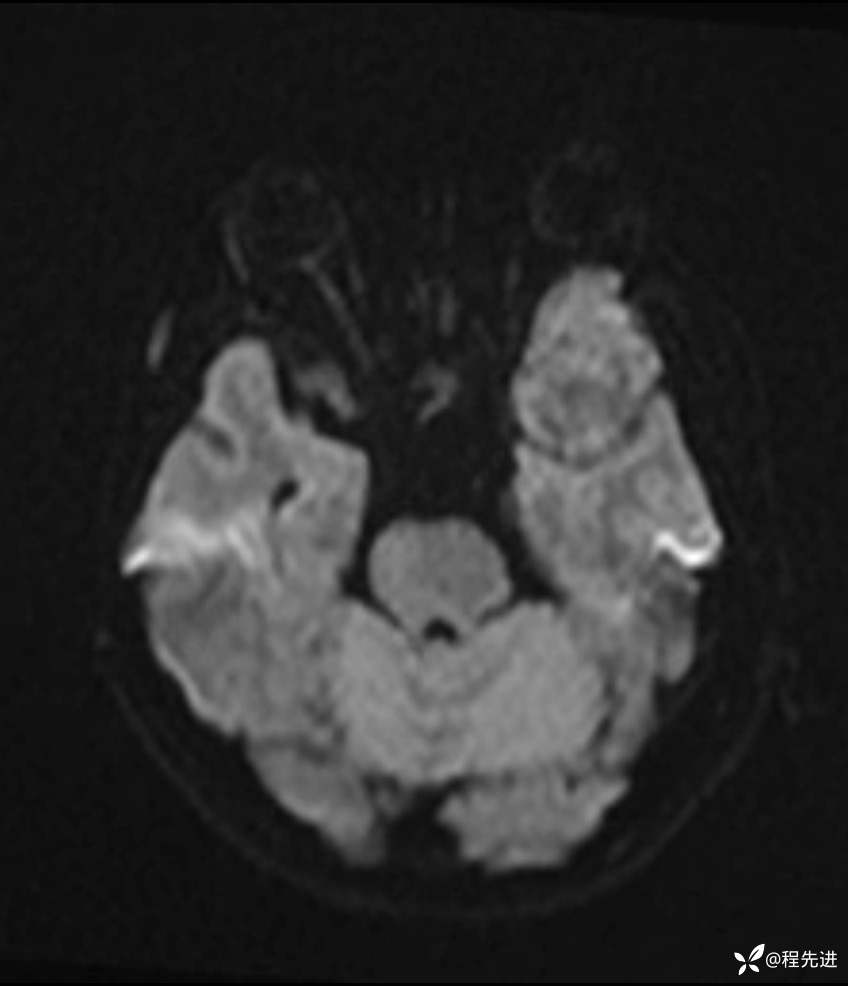

DWI: